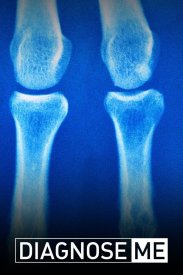

Поставьте мне диагноз

Вы увидите, как врачи становятся настоящими детективами, решая удивительные и странные случаи, которые не поддаются ни одному из одарённых специалистов. Невероятные повороты событий, когда врачам прих...